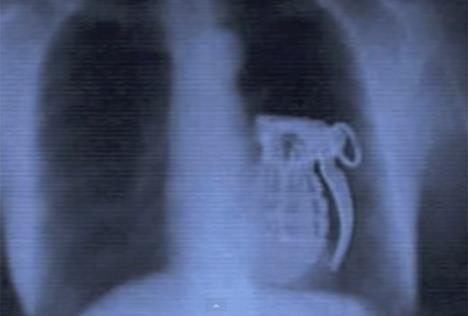

LUDOSTI: 25 najčudnijih stvari koje je rendgen snimio u ljudskom telu